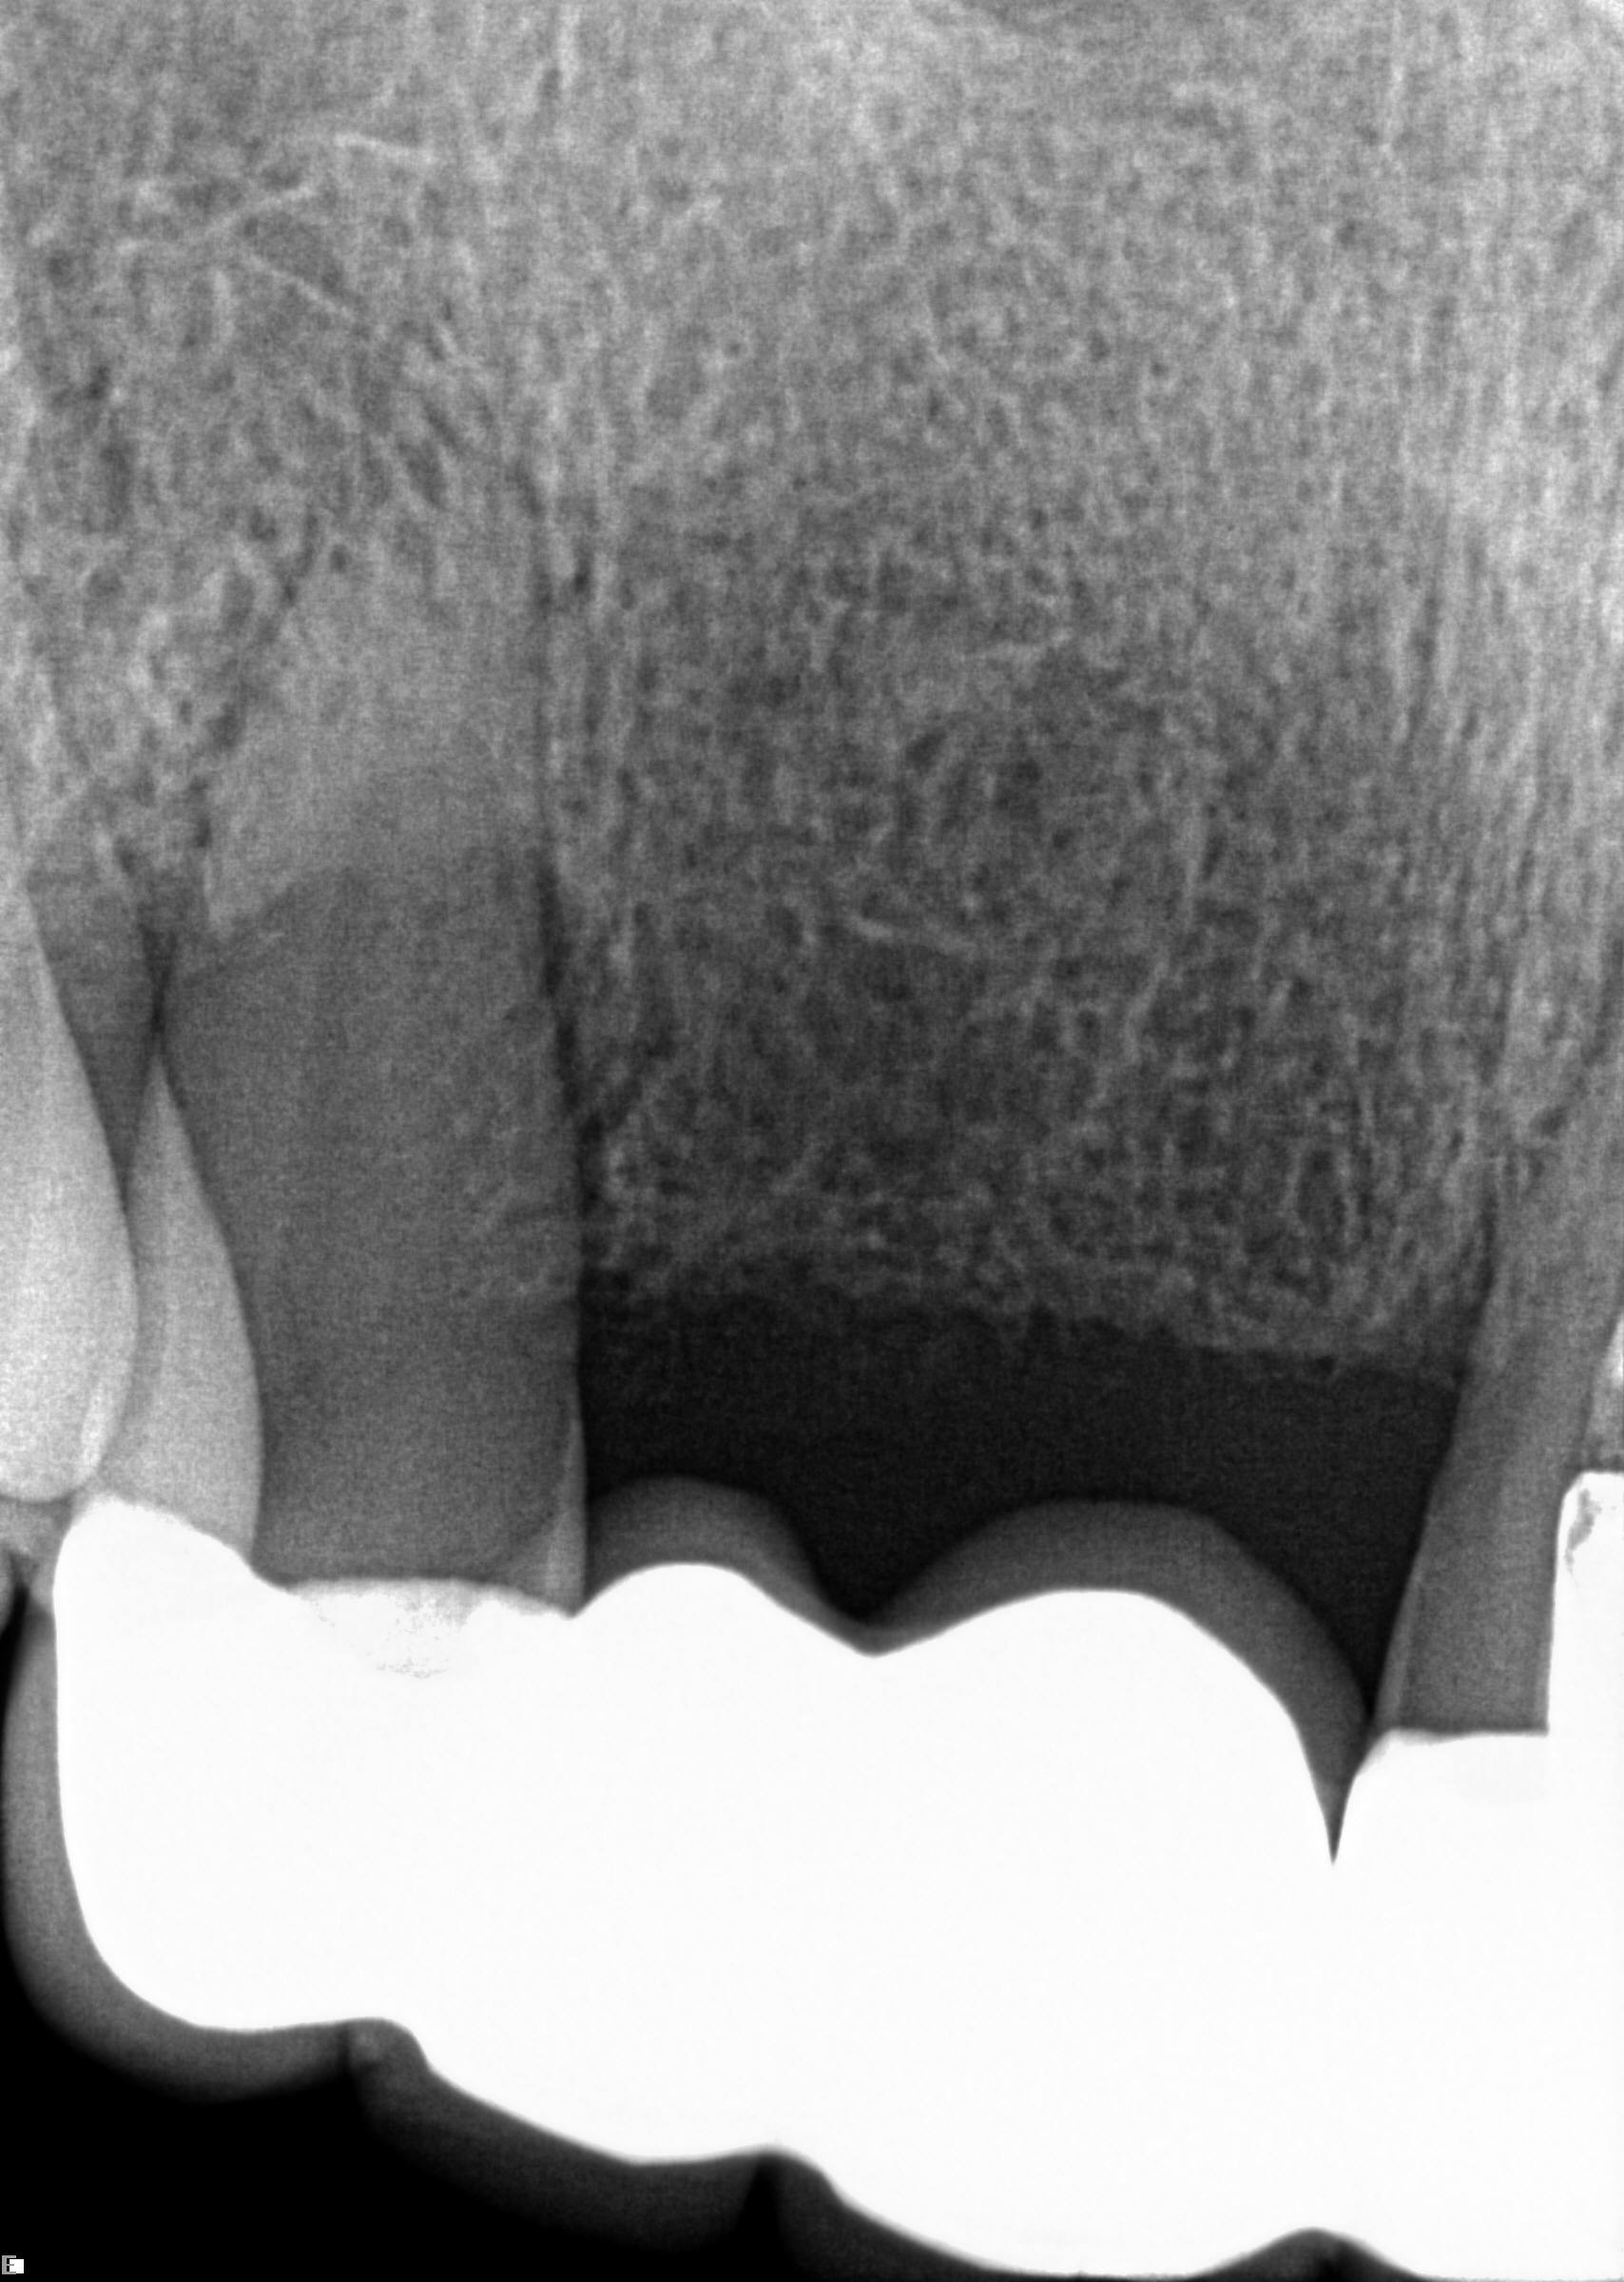

(14.) Integration confirmation on Nos. 12 and 13 at 6 months with temporary abutments and good soft tissue maturation.

Figure 14